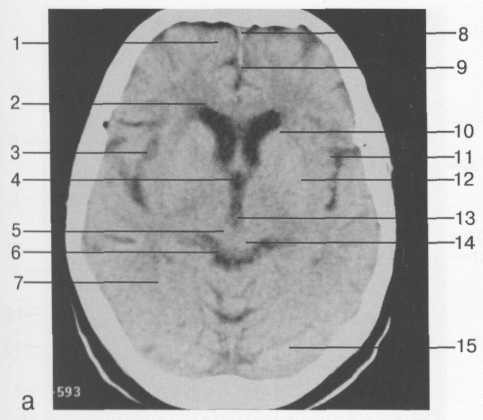

Компьютерные томограммы головы производят при горизонтальном положении пациента, выделяя изображения отдельных слоев черепа и головного мозга (рис. 34).

Рис. 34.         КТ изображение  головы в аксиальной плоскости. Определяется перелом затылочной кости на уровне внутреннего затылочного выступа справа.

Специальной подготовки к исследованию не требуется. Полное исследование головы состоит из 12--17 срезов (в зависи­мости от толщины выделяемого слоя). Об уровне среза можно судить по конфигурации желудочков мозга; они, как правило, видны на томограммах. Часто при КТ мозга используют методику усиления путем внутривенного введения водорастворимого контрастного вещества.

На компьютерных и магнитно-резонансных томограммах хорошо разли­чимы полушария большого мозга, мозговой ствол и мозжечок. Можно дифференцировать серое и белое вещество, очертания извилин и бо­розд, тени крупных сосудов, ликворные пространства. Как КТ, так и МРТ наряду с послойным изображением могут реконструировать трех­мерное отображение и анатомическую ориентацию во всех структурах черепа и головного мозга. Компьютерная обработка позволяет полу­чить увеличенное изображение интересующей врача области.

При изучении структур мозги МРТ имеет некоторые преимущества перед КТВо-первых, на MP-томограммах более четко различаются структурные элементы головного мозга, отчетливее дифференцируются белое и серое вещество, все стволовые структуры. На качестве магнитно-резонансных то­мограмм не отражается экранирующее действие костей черепа, ухудшаю­щее качество изображения при КТ. Во-вторых, МРТ можно производить в разных проекциях и получать не только аксиальные, как при КТ, но и фронтальные, сагиттальные и косые слои. В-третьих, это исследование не связано с лучевой нагрузкой. Особым достоинством МРТ является возмож­ность отображения сосудов, в частности сосудов шеи и основания головно­го мозга, а при контрастировании гадолинием -- и мелких сосудистых вет­вей (см. рис. 35 и 36).

Рис. 36. Изображения аксиальных срезов КТ и МРТ области головы над уровнем  четвертого желудочка:

а -- аксиальный срез КТ; б -- аксиальный срез МРТ

(Т1-ВИ); в -- аксиальный срез МРТ (Т2-ВИ).

1 -- лобная доля; 2 -- лобный рог бокового желудочка; 3 -- латеральная щель мозга; 4 -- третий желудочек; 5 -- ножка мозга; 6 -- цистерна четверохолмия; 7 -- височная доля; 8 -- верхний сагиттальный синус; 9 -- серп мозга; 10 -- головка хвостатого ядра; 11 -- кора островка; 12 -- скорлупа; 13 -- внутренняя вена мозга; 14 -- четверохолмие; 15 -- полушарие мозжечка; 16 -- зрительный нерв; 17 -- височный рог бокового желу­дочка; 18 -- гиппокамп; 19 -- передняя долька мозжечка; 20 -- хиазма; 21 -- внутренняя сонная артерия; 22 -- охватывающая цистерна; 23 -- четвертый желудочек; 24 -- прямая извилина; 25 -- ольфакторная бо­розда; 26 -- средняя мозговая артерия; 27 -- червь; 28 -- затылочная доля; 29 -- клетчатка орбиты; 30 -- пе­редняя мозговая артерия; 31 -- межножковая цистерна.

Представленные изображения  в полной мере дают возможность оценить структуры головного мозга.